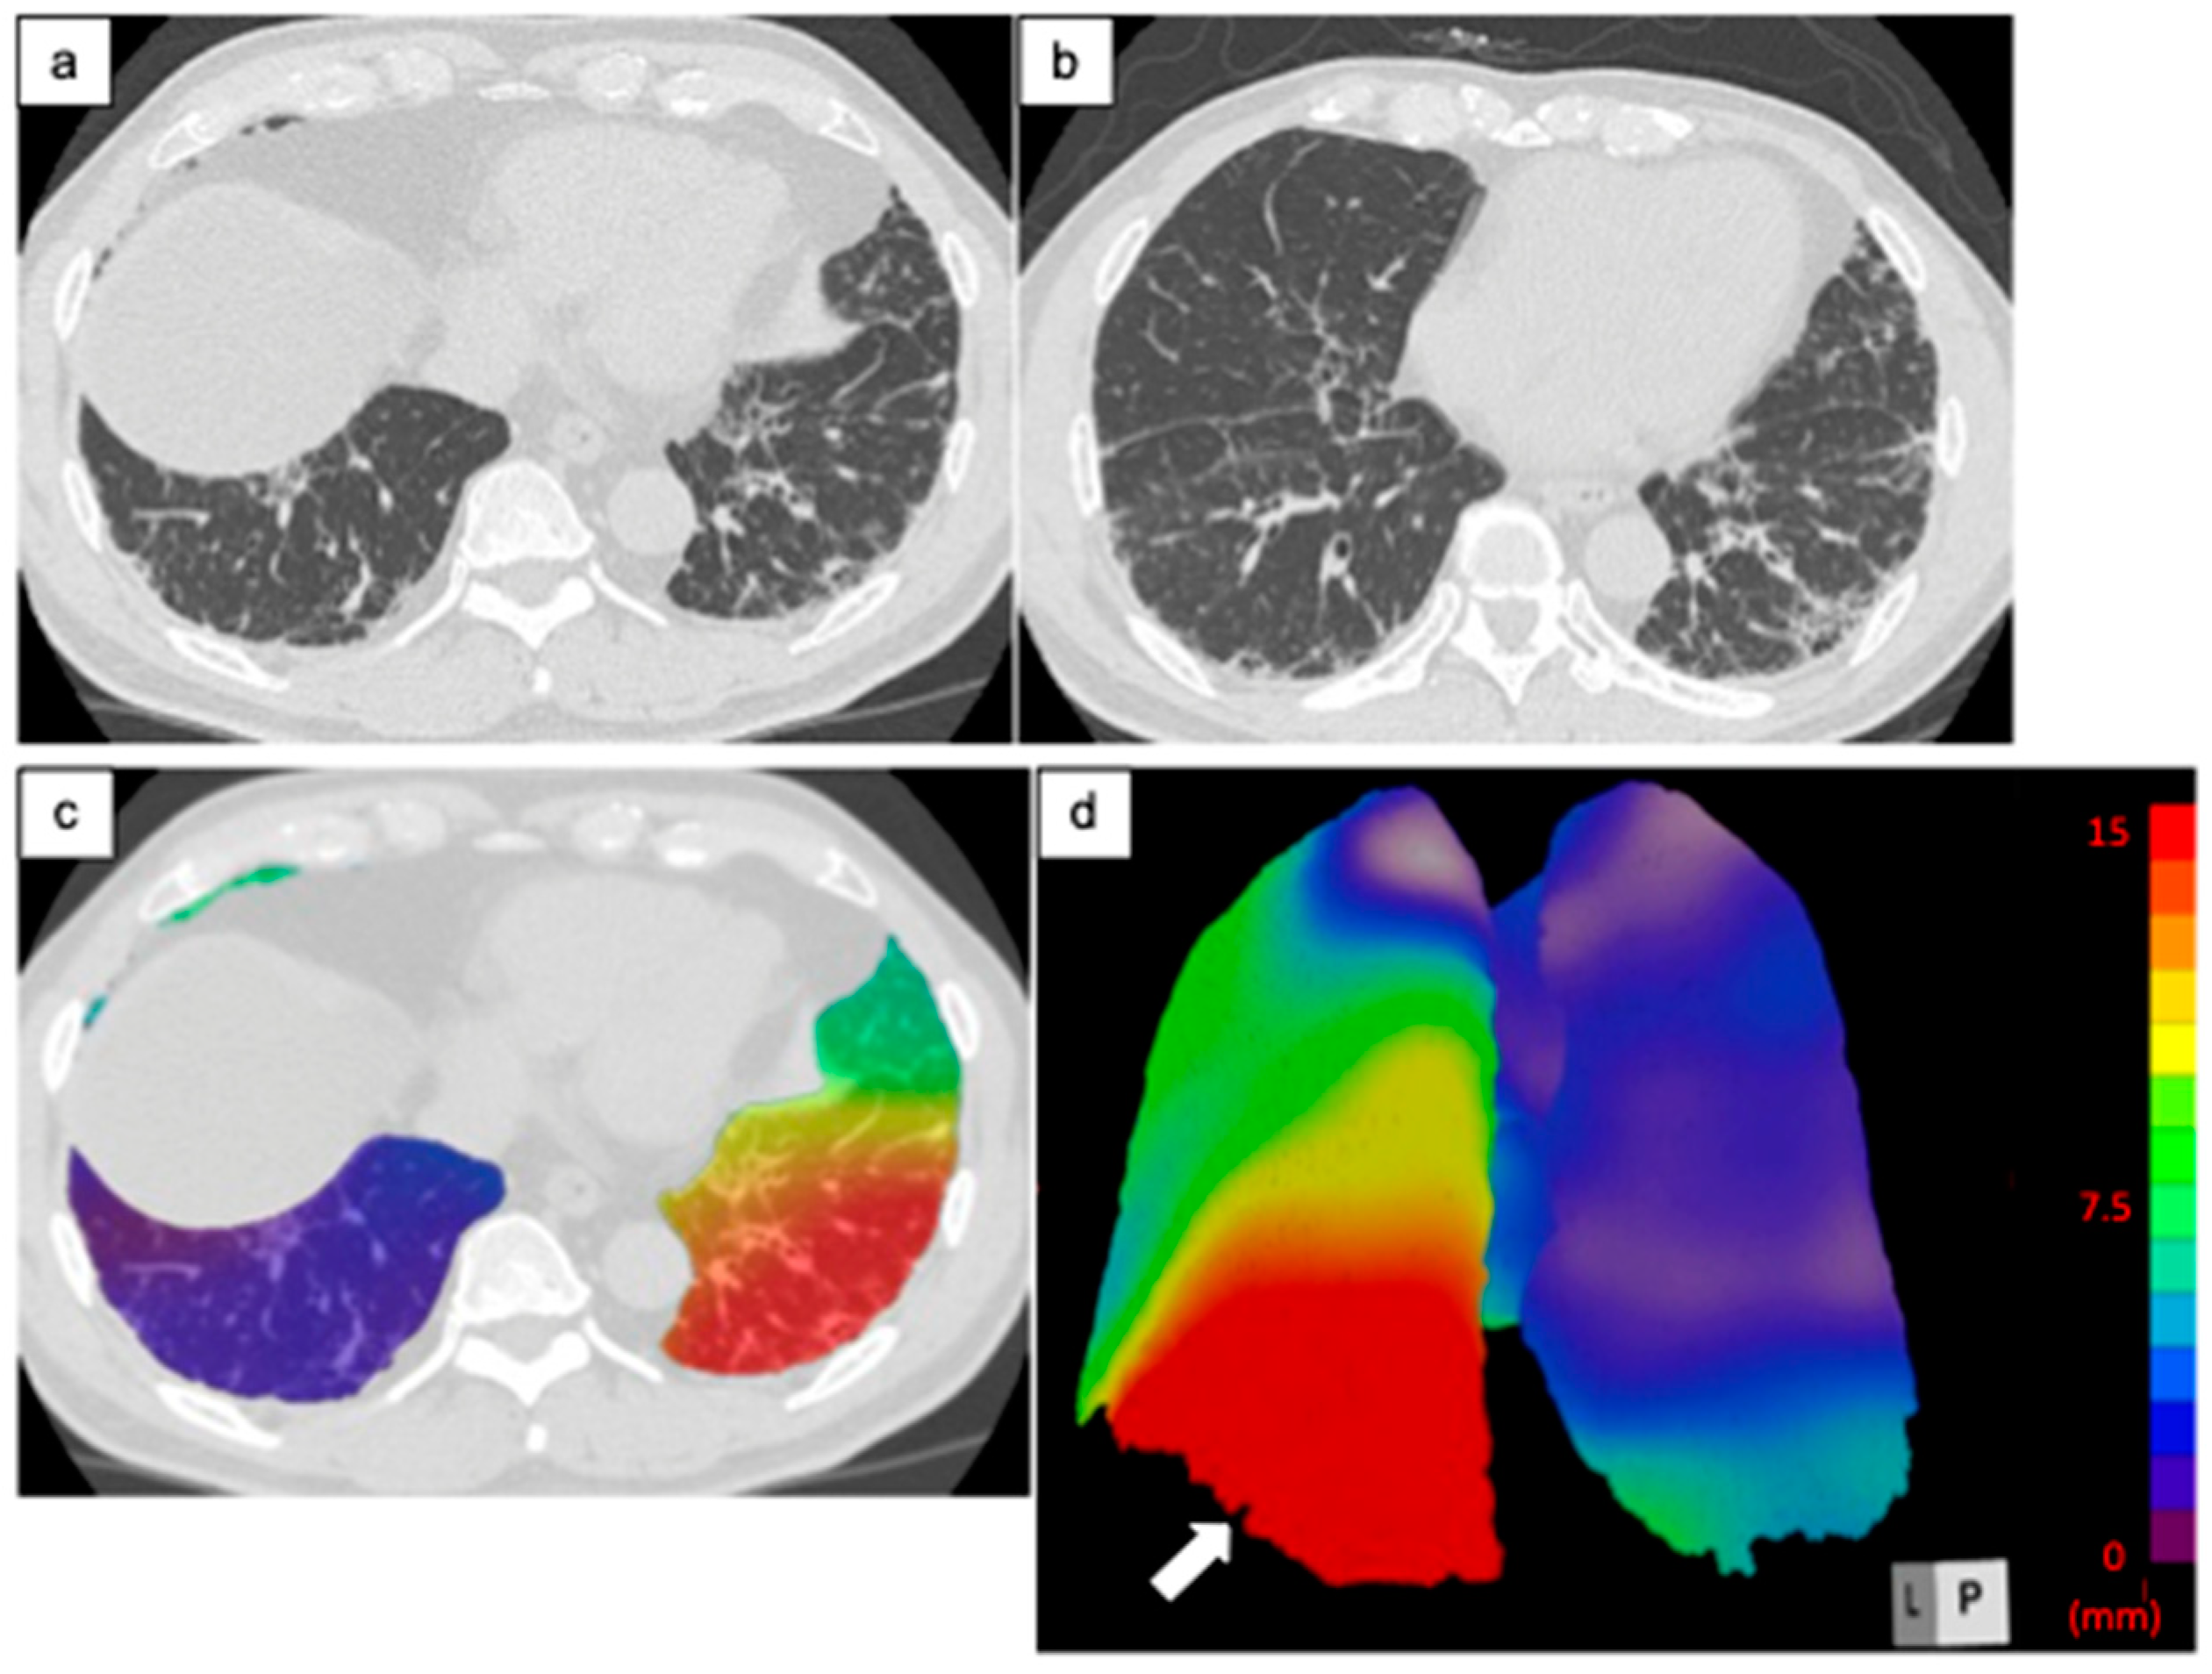

2.3.1. Architectural Distortion Measurement by 3D-AD

3.2.1. Architectural Distortion Measurement by 3D-AD